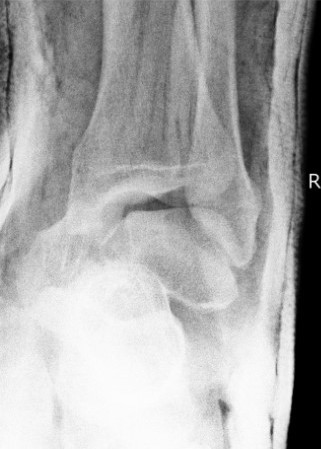

Xray / CT

Ensure no displacement / malalignment

Canale view

- evaluates talar neck

- foot everted 15 deg

- look for medial shortening / varus

Xrays

| AP | Lateral | Canale View |

|---|---|---|

| Entry point of the screws |

Evaluate neck reduction

|

Evaluates the neck reduction |

Lateral off articular surface Medial through articular cartilage |

Depth of screws |

Beam angled 75o to foot Foot 15o pronated |